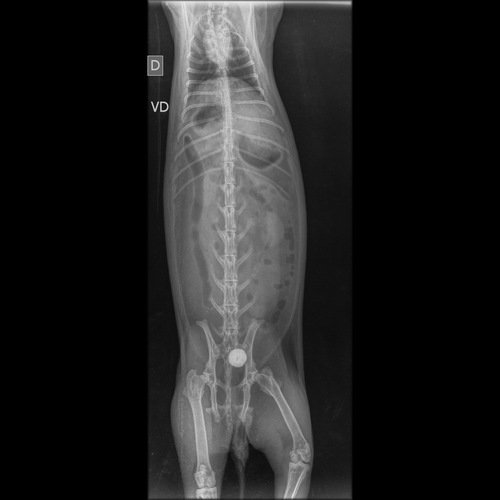

Oi, meu nome é Laisla, estou criando essa vakinha para ajudar meu coelho a fazer uma cirurgia de cistotomia. Hoje pela parte da manhã ele acordou com um pouco de sangue ao redor, levei no veterinário e descobrimos esse problema. Infelizmente não consigo manter o custo da cirurgia. Quem puder ajudar agradeço de coração. Deus abençoe e retribua o dobro ❤️🙏🏻🐰